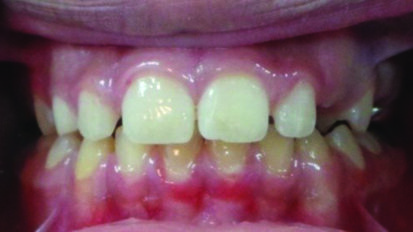

Avulsion in Paediatric Dentistry: Management of a Double Dental Emergency in a Child

General dental practitioners and paediatric dentists face real dental emergencies that effect children, especially dental trauma. Avulsion is considered, in...